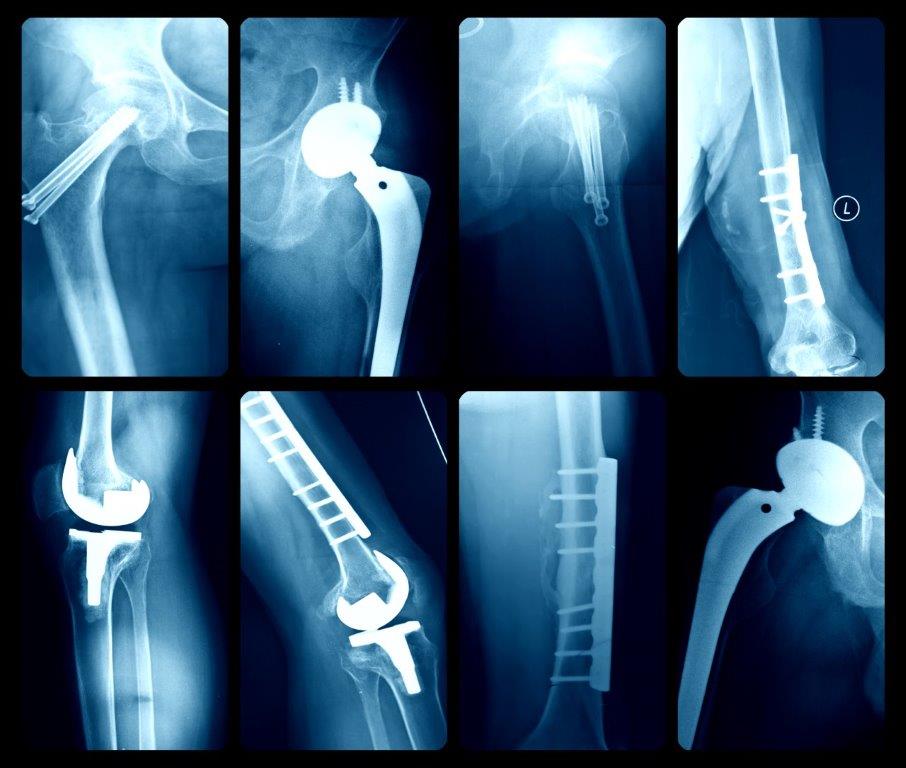

Traumatología y Ortopedia

La traumatología es la rama de la medicina que se dedica al estudio de las lesiones del aparato locomotor. La especialidad es médico-quirúrgica, y los médicos que la practican se llaman traumatólogos

Su ámbito se extiende más allá del campo de traumatismo mayores; abarca el estudio de las enfermedades congénitas o adquiridas que afectan al aparato locomotor, especialmente de aquellas que precisan tratamiento con cirugía ortopédica, prótesis u órtesis. Sin embargo, no todas las enfermedades del aparato locomotor entran dentro del campo de la traumatología, pues gran parte de los problemas de salud que afectan a las articulaciones se incluyen en el ámbito de la reumatología o la fisiatría que son otras especialidades médicas diferentes. Algunas de las enfermedades de las que se ocupa la traumatología son las fracturas y luxaciones de los huesos, las lesiones de ligamentos, tendones y músculos, también los tumores óseos y numerosas afecciones de la columna vertebral como la hernia discal y la escoliosis.

La ortopedia es una disciplina relacionada que atiende los traumatismos a través de aparatos ortopédicos, rehabilitación y otras terapias.